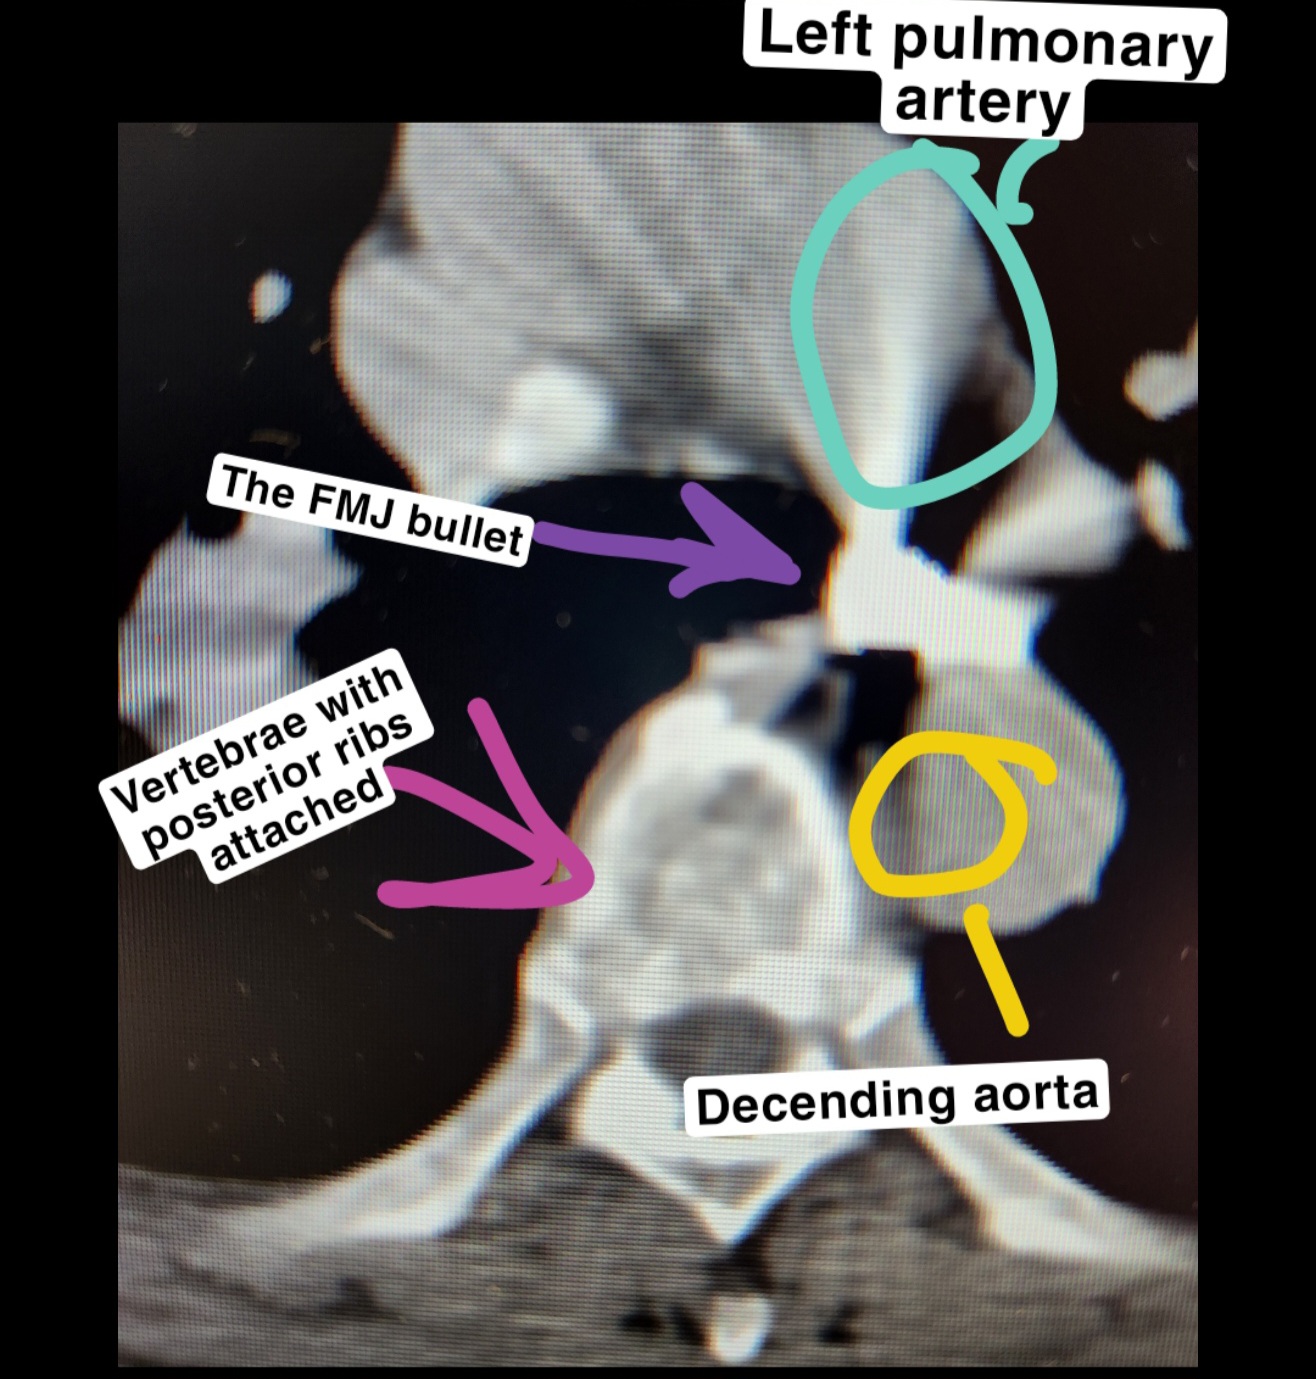

The expansion of hollowpoints isn't just good for preventing collateral, it also helps eliminate your target. This patient of mine, also in Detroit funny enough, got shot with what appears to be a 45acp FMJ given it's size. The bullet is literally sitting against his pulmonary and decending aortas, meaning just 1mm of expansion would have killed him. This fucker bullied our 60 year old secretary until she had to leave the desk and come to us near tears, and I regret the shooter didn't use a quality hollowpoint. Hopefully the next guy does, because with how poisonous this guy was to be around there will be a next time he gets shot in the great city of Detroit.

Here is a pic of the bullet laying against both the left pulmonary artery and decending aorta. I have now shown you the article of an event and provided photo evidence of how expansion can and does matter for lethailty. The streaking is from beam hardening artifact since the bullet is made of very dense lead, which is why we tell patients to remove jewelry and jeans (button and zipper) ect. Before their scans. It obscurs the anatomy otherwise.

>>64449141

I'd wager few people here are trained in radiology or how to interpret imaging for anatomy and foreign objects.

>>64449149

Good idea.

Worth noting internal images of the body are flipped left to right, so the left pulmonary labeled is on the right side of the picture.

The pulmonary artery and decending aorta have every drop of blood in your body pumped through them in roughly 80 seconds. Pulmonaries are the path from your heart to your lungs, and once that blood is oxygenated your body pumps it through your body via the decending aorta. If pierced you bleed out and die before you could even walk from the parkinglot to the ER entrance.

>>64449187

>Either he was shot through a significant barrier, or that's not a .45 ACP. Either way a hollowpoint would have likely resulted in less penetration.

We have tools on the scanner to measure objects for cancers and cyst and such and used those to measure the bullet at the time. It matched about what a 45acp bullet should be, but this was 2 years ago and I don't have any pictures of those measurements so you're either going to have to measure the ribs and vertebrae and then based on that measurement and the average size of those pieces of anatomy get a measure of the bullet yourself, or just trust me on this one. Here is another internal picture of the same patient below the bullet if you want to put in your own legwork. I put in enough leg work drawing diagrams and finding articles of FMJ overpenetration causing a death only for folks to go "nuh uh", so this will be my last post on the subject.

It's worth noting that there are bullet fragments seen around the patient's right scapula seen here >>64449110 (remember, in radiology anatomy is flipped left/right) so as to your barrier penetration that could be the cause. Also worth noting is that the bullet is now facing the direction it entered, meaning it tumbled a bunch after impact. Quality hollow points are designed to penetrate things like auto glass and still travel through a persons arm and chest to the heart.